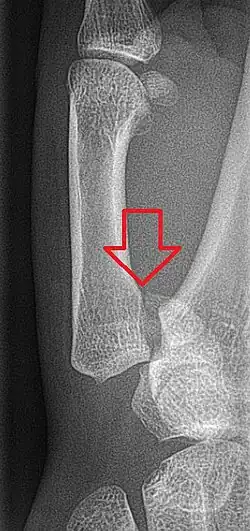

| Bennett's fracture on x-ray | |

Bennett's fracture or Bennett fracture is a type of partial broken finger involving the base of the thumb, and extends into the carpometacarpal (CMC) joint.[1]

This intra-articular fracture is the most common type of fracture of the thumb, and is nearly always accompanied by some degree of subluxation or frank dislocation of the carpometacarpal joint.